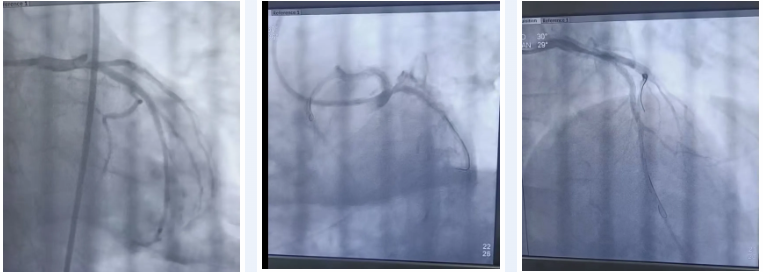

在患者血压极不稳定的情况下,胸痛中心团队争分夺秒行急诊冠脉造影,结果显示,患者前降支近段完全闭塞——这正是引发「电风暴」的根源。介入团队迅速植入支架,当血管恢复 TIMI III 级正常血流时,监护仪上的心律终于趋于平稳,这场与死神的 「拉锯战」,以医护人员的胜利告终。